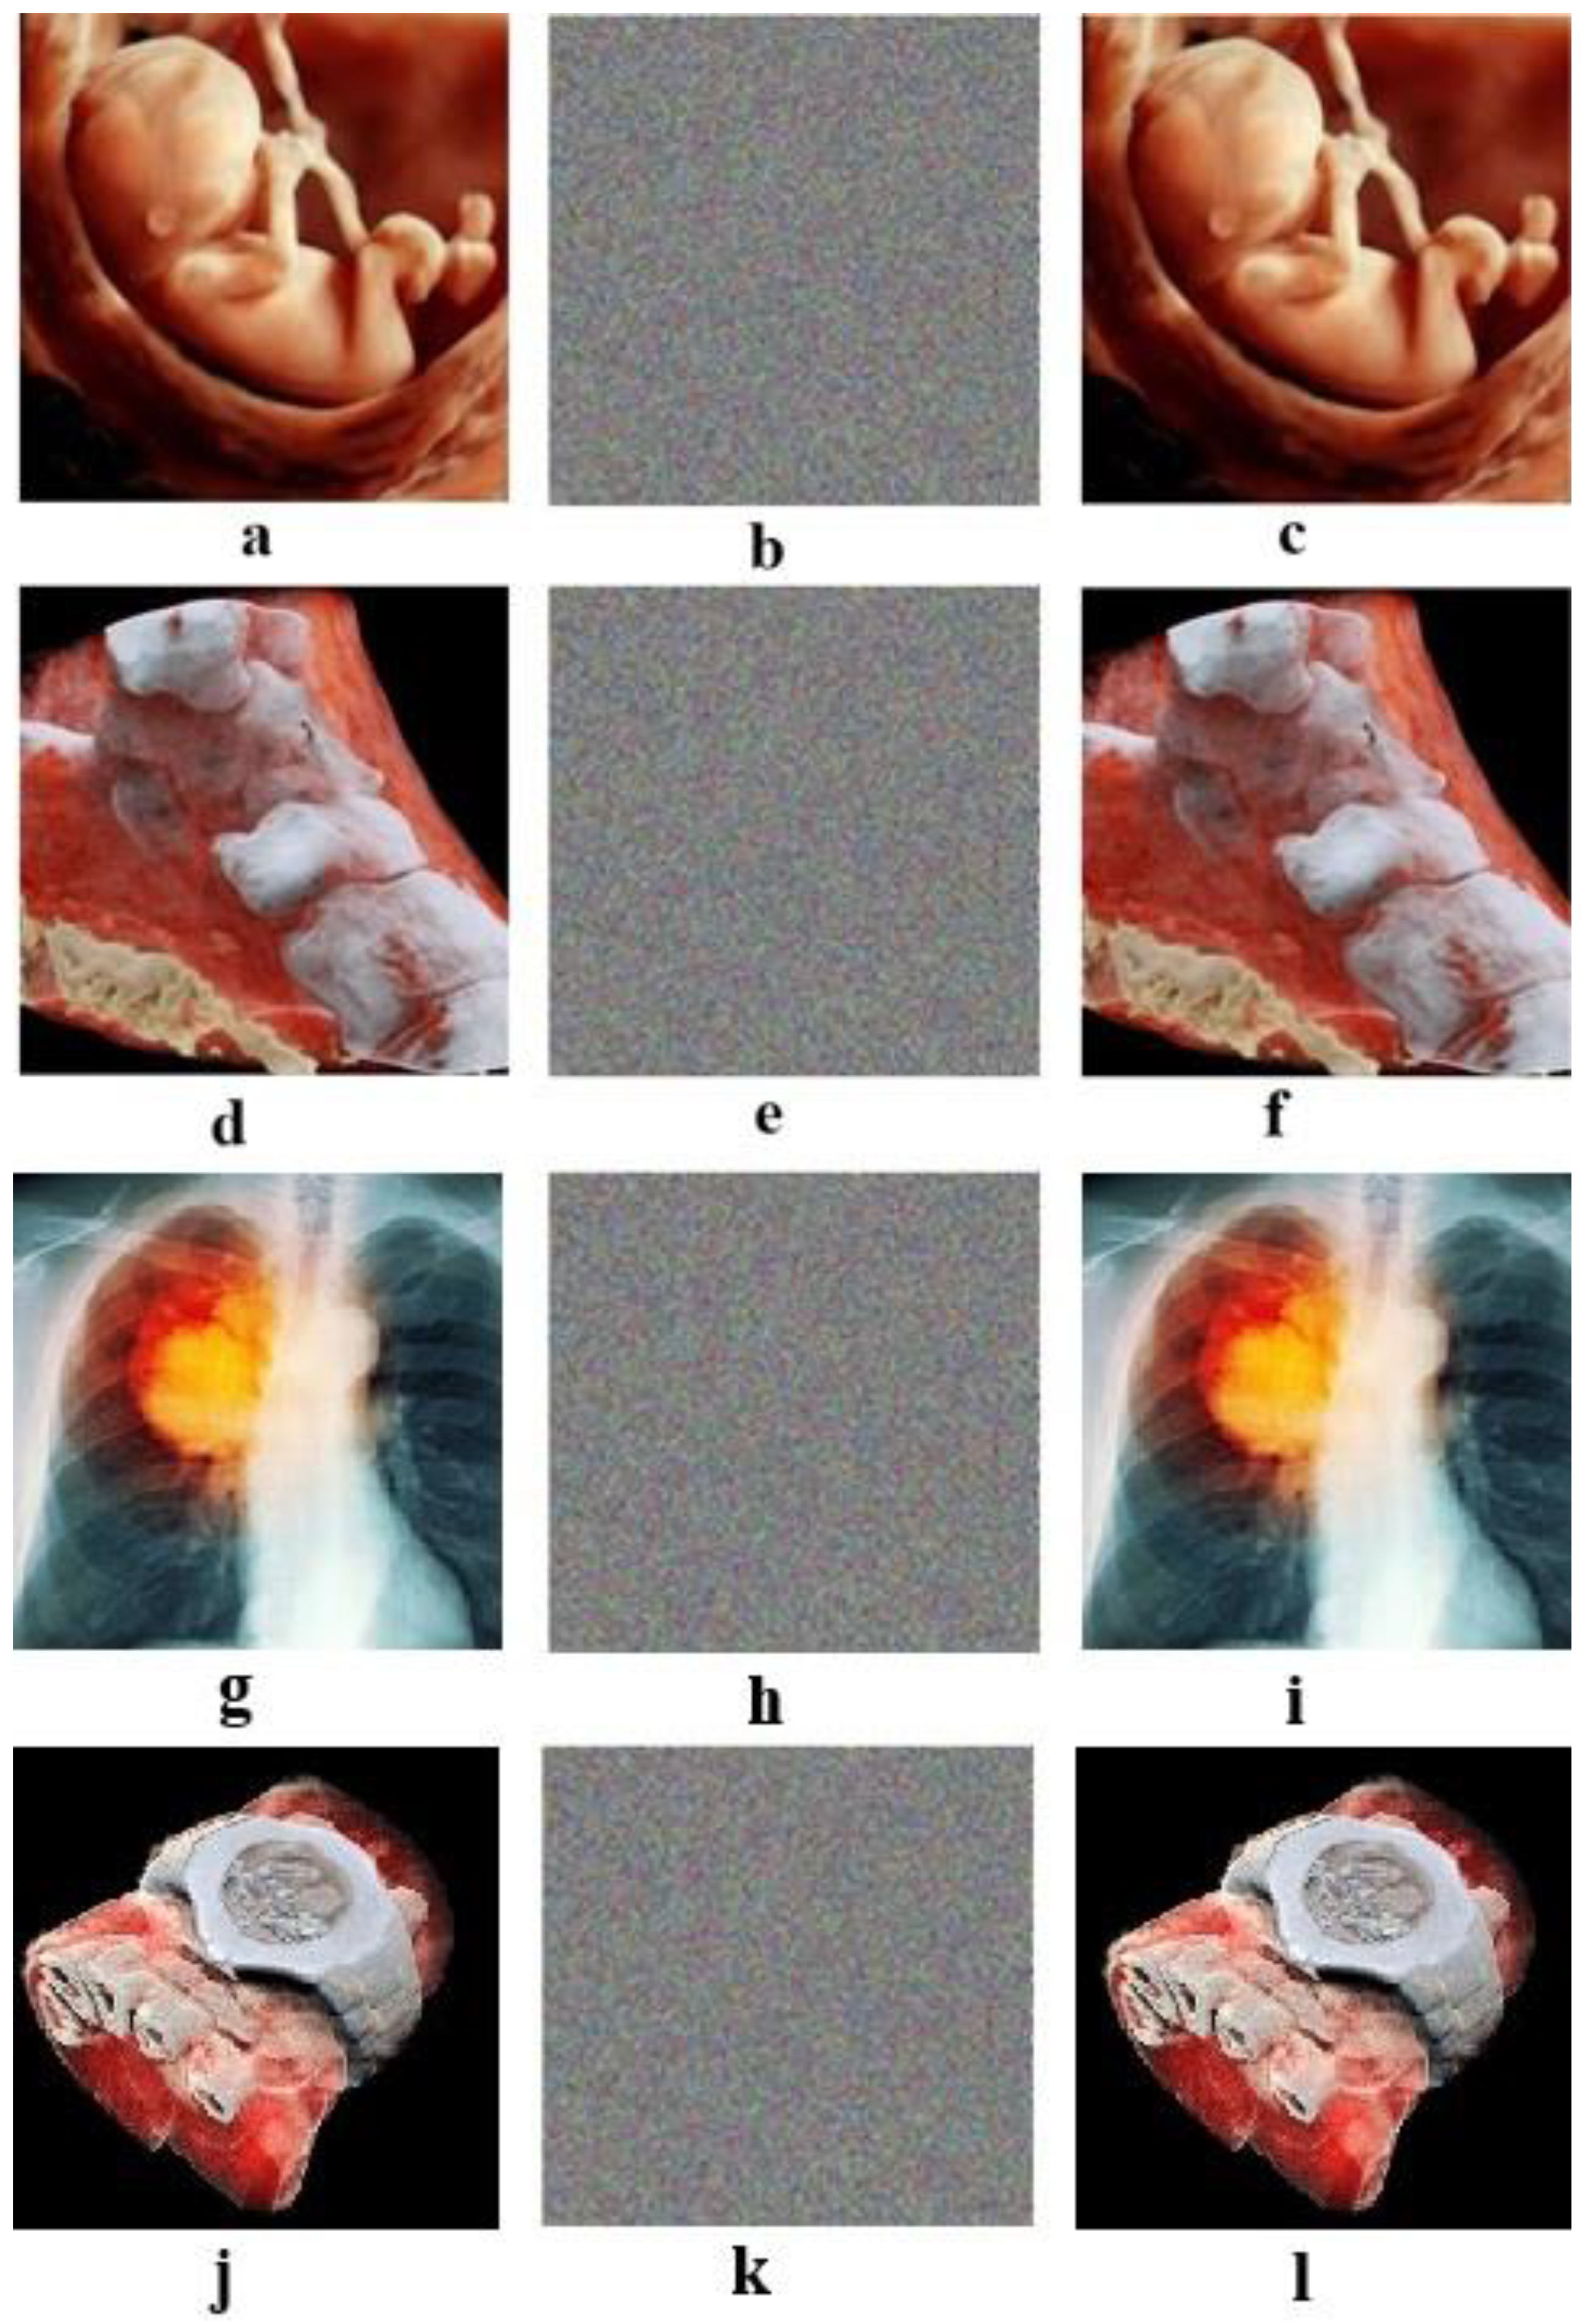

4.8. Known-Plain Image and Chosen-Plain Image Analysis

Clearly, some specific images are selected to test the selected plain-text attack, like a full-white image in Figure 8a and a full-black image in Figure 8d. The results are shown in Figure 8, which indicate that the cryptology is appropriate for these specific images and can resist the chosen-plain-text attack. In Table 6, we can see the entropy values for all-white and all-black images. It can be seen that all the values that are obtained are close to 8, indicating the suitability of the proposed algorithm.

Figure 8.

Selected plain-image test for white and black images, display (a) the full-white image, (b) the cipher image of panel (a), (c) the histogram of channel R (b), (d) the full-black image, (e) the cipher image of panel (d), and (f) the histogram of channel R.

Table 6.

Information entropy of the full-black image and full-white image.